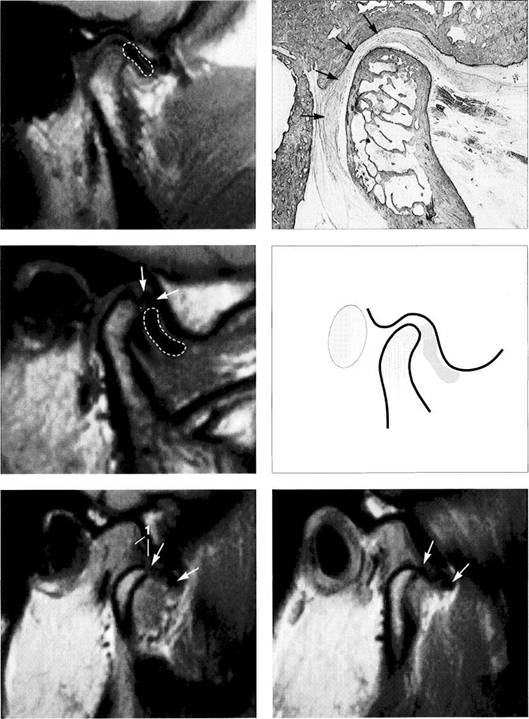

Normal joint

Left: Macroscopic anatomical pre­paration of a right temporo­mandibular joint with normal disk position. The pars posterior (1), pars anterior (2), pars media (arrow), and condyle (3) can be clearly seen.

Right: In spite of the reduction in signal caused by formalin fixation, the corresponding slice in MRI shows the identical relationships between the disk (1,2) and condyle

Medial disk displacement

Left: Formalin-fixed preparation from a right joint. In this anterosu-perior view, the displacement of the disk (arrows) toward the medial is evident.

Lateral pterygoid muscle

Lateral pole

Medial pole

Right: MRI in the angled coronal plane confirms the medial disk po­sition (arrows). The contours of the fossa and condyle are reproduced precisely.

Shape of the pars posterior

Left: Macroscopic anatomical pre­paration of a right articular disk showing its positional relationship to the condyle. The posteroinferior edge of the pars posterior (1) shows a small triangular area of fi­brosis (arrows).

Right: In spite of the sharply re­duced signal emission resulting from formalin fixation, even this type of change is accurately repro­duced (arrows). Here the use of a combination of T1 and T2 weight­ing is often helpful.

Reproduction of Anatomical Detail in MRI

Fibrosis of the bilaminar zone

Left: Formalin-fixed preparation of the centromedial part of a left tem­poromandibular joint with localized fibrosis of the bilaminar zone (ar­rows).

Pars posterior

Right: The MRI accurately repro­duces the abnormality (arrows) dis­tal to the flattened pars posterior. The contour of the condyle is indi­cated by a broken line.

Presumed "posterior disk displacement"

Left: Macroscopic preparation of a left temporomandibular joint with normal positioning of the pars an­terior (1) and pars posterior (2) in the lateral portion of the joint. The retrodiskal structures appear thick­ened.

Right: In an MRI there appears at first glance to be a posterior disk displacement (arrows). Under clos­er inspection, however, it can be seen that the pars anterior (1) and pars posterior (2) lie in correct rela­tion to the condyle.

Left: A view of the disk and the bil­aminar zone after further prepara­tion again reveals the correct posi­tional relationships. Here the pars anterior (1) and pars posterior (2) can be identified more readily. The presumed "posterior disk displace­ment" is a false positive interpreta­tion of the fibrosis of the bilaminar zone (arrows).

Right: MRI of the same joint shown in Figure 427.

Disk perforation and osteoarthrosis

Left: Anatomical preparation of a left temporomandibular joint with arthrotic changes (black arrows) and extensive disk perforation (white arrows). In the anterior re­gion only a part of the former pars anterior (1) can still be recognized.

Right: MRI shows similar conditions. The cortical layer of the arthrotic condyle is thickened extensively (arrows). The remainder of the pars anterior (1) can still be distin­guished.